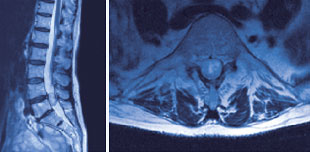

Abb. 2

Grosses Lipom (Fettzell-Tumor), welches sich langstreckig nahezu in der gesamten Lendenwirbelsäule innerhalb der Rückenmarkshaut ausdehnt.

In aller Regel (40%) bilden sich hier gutartige und nur langsam wachsende Tumore ohne eigene Ableger. Die sogenannten Meningeome gehen von der Rückenmarkshaut, die sogenannten Neurinome von einer Nervenwurzel aus. Die Meningeome befinden sich meist im Bereich der Brustwirbel und kommen gehäuft bei Frauen nach der Menopause vor. Die Neurinome (Abb. 1) gehen hingegen von den Nervenwurzeln selbst aus und können an jeder Stelle, teils sogar gleichzeitig an mehreren Stellen, vorkommen. Selten durchbrechen sie die Rückenmarkshaut und dehnen sich in den Wirbelkanal aus. Die Meningeome und die Neurinome sind gut begrenzt, üben aber aufgrund ihres Wachstums einen zunehmenden Druck auf die Nervenstrukturen aus. Sie können sich somit durch örtliche, häufig während der Nacht auftretende Schmerzen oder aber auch durch Lähmungen oder Ausfälle der Sensibilität bemerkbar machen. In seltenen Fällen können Tumore von anderen Strukturen innerhalb der Rückenmarkshaut ausgehen (Abb. 2).